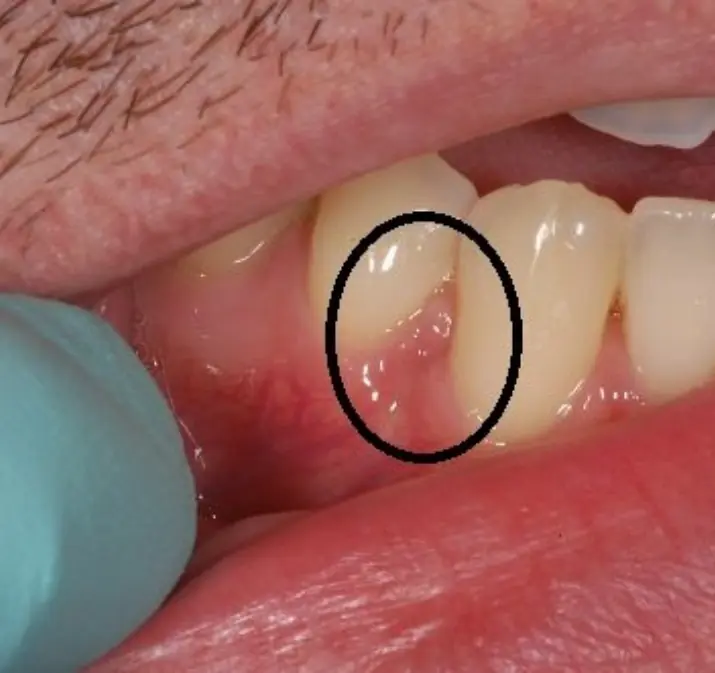

The image highlighting the area between the teeth and gums serves as a reminder that early warning signs often appear in places people rarely notice. Understanding these symptoms can help individuals act quickly and protect their dental health before more serious issues develop.

One of the most common early symptoms is mild swelling or redness around the gum line. This condition, known as gingivitis, occurs when plaque—a sticky film of bacteria—builds up on teeth.

People with gingivitis may notice that their gums appear slightly puffy or darker in color than usual.

The highlighted area between the teeth and gums in the image demonstrates how subtle early symptoms can be. Many people overlook these small changes until discomfort becomes more noticeable.

By paying attention to early warning signs such as gum redness, swelling, or bleeding, individuals can take action early and prevent more serious dental problems in the future.